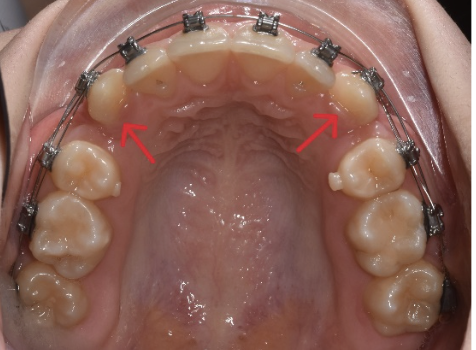

S-a realizat extractia a 2 premolari: